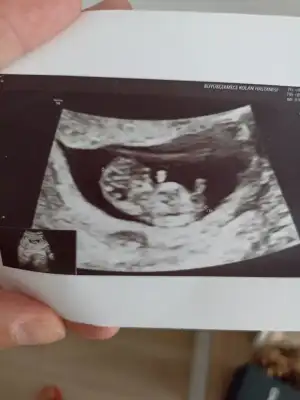

Çok teşekkür ederim.🥰 Eller kollar hareketlenmiş bir de. Öyle görünce içim kıpır kıpır oldu.Bir kızım var bir de oğlum olsun isterim.Ama kız olursa da cok mutlu olurum.Gercekten hiç fark etmez. Evlat sonuçta Rabbim hayırlısı neyse sağlıklı bir şekilde onu nasip eder inşallah.Kızıma hamileyken rüyamda kız olacağını görmüştüm.Bunda bebek gördüm ama cinsiyetini görmedim.@lolaylty 6+1 ve 7+1 ultrason görüntüsüne göre erkek demişti siz de kız dediniz.Hangisi olacak bakalım 😄 Hayırlısı olsun.Rabbim sizin bebeğinizi de gönlünüze göre sağlıklı bir sekilde kucağınıza almayı nasip eder inşallah.🙏💞